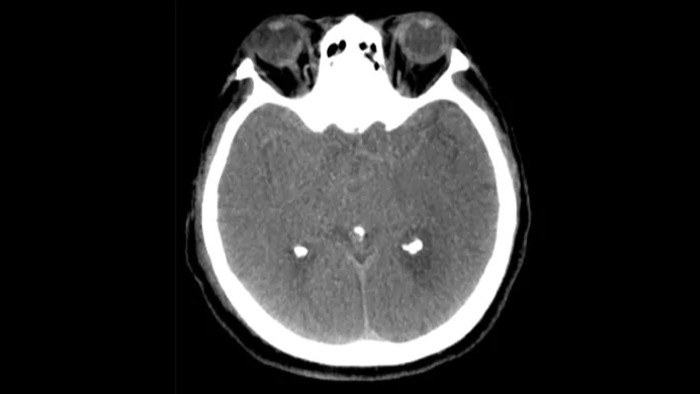

SmartCT Soft Tissue выполняет КТ-подобную визуализацию мягких тканей и дополняет диагностику инсульта тремя способами. Технология бесконтрастного сканирования помогает выявить ишемические изменения на ранних стадиях. Сканирование ранней фазы помогает определить проксимальную окклюзию. Сканирование поздней фазы с усилением контраста направлено на обнаружение коллатералей.

Технология Dual View для одновременного просмотра ранней и поздней фаз КТ-подобной визуализации способствует определению ишемической полутени и обеспечивает визуализацию наполнения коллатералей.

Используйте изображения, полученные с помощью SmartCT (КТ-подобные), с решением Neurovascular Suite, чтобы убедиться в успешности лечения и осуществить проверку на наличие кровотечений.